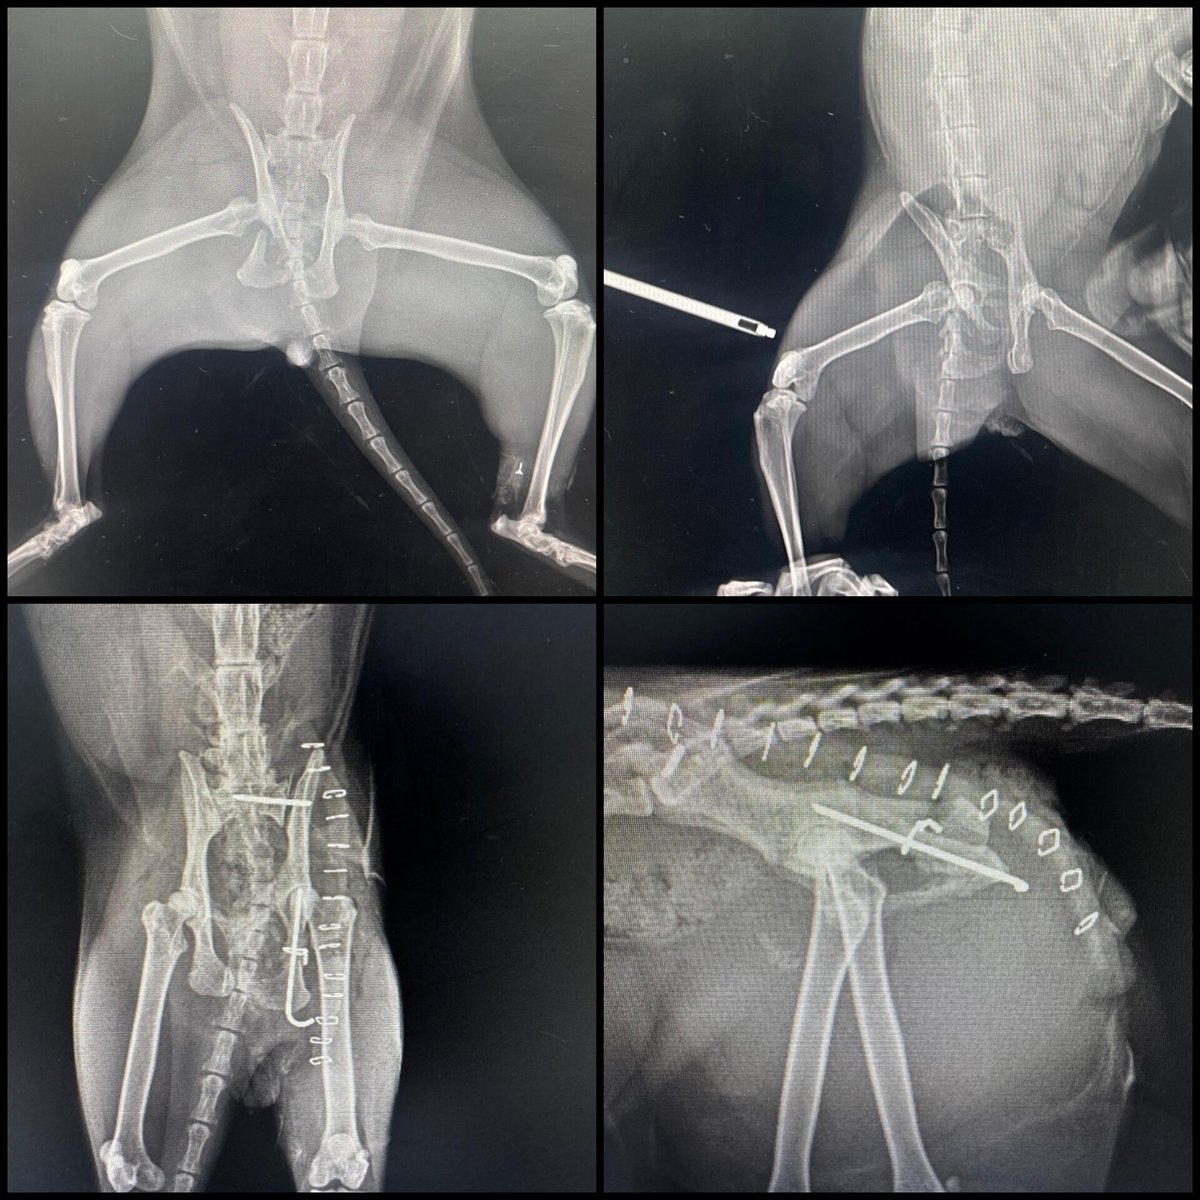

Yavrum kliniğe ulaştı yoğun bakıma alındı. Ne kan tahlillerinde ne de röntgeninde herhangi bir sıkıntı gözükmemiş. Nörolojik bir durum olabilir ona da MR ya da tomografi gerekir ama anestezi alamaz şu an direkt masada kalır, durumu çok kritik denildi😪 Dua edin çocuğuma.